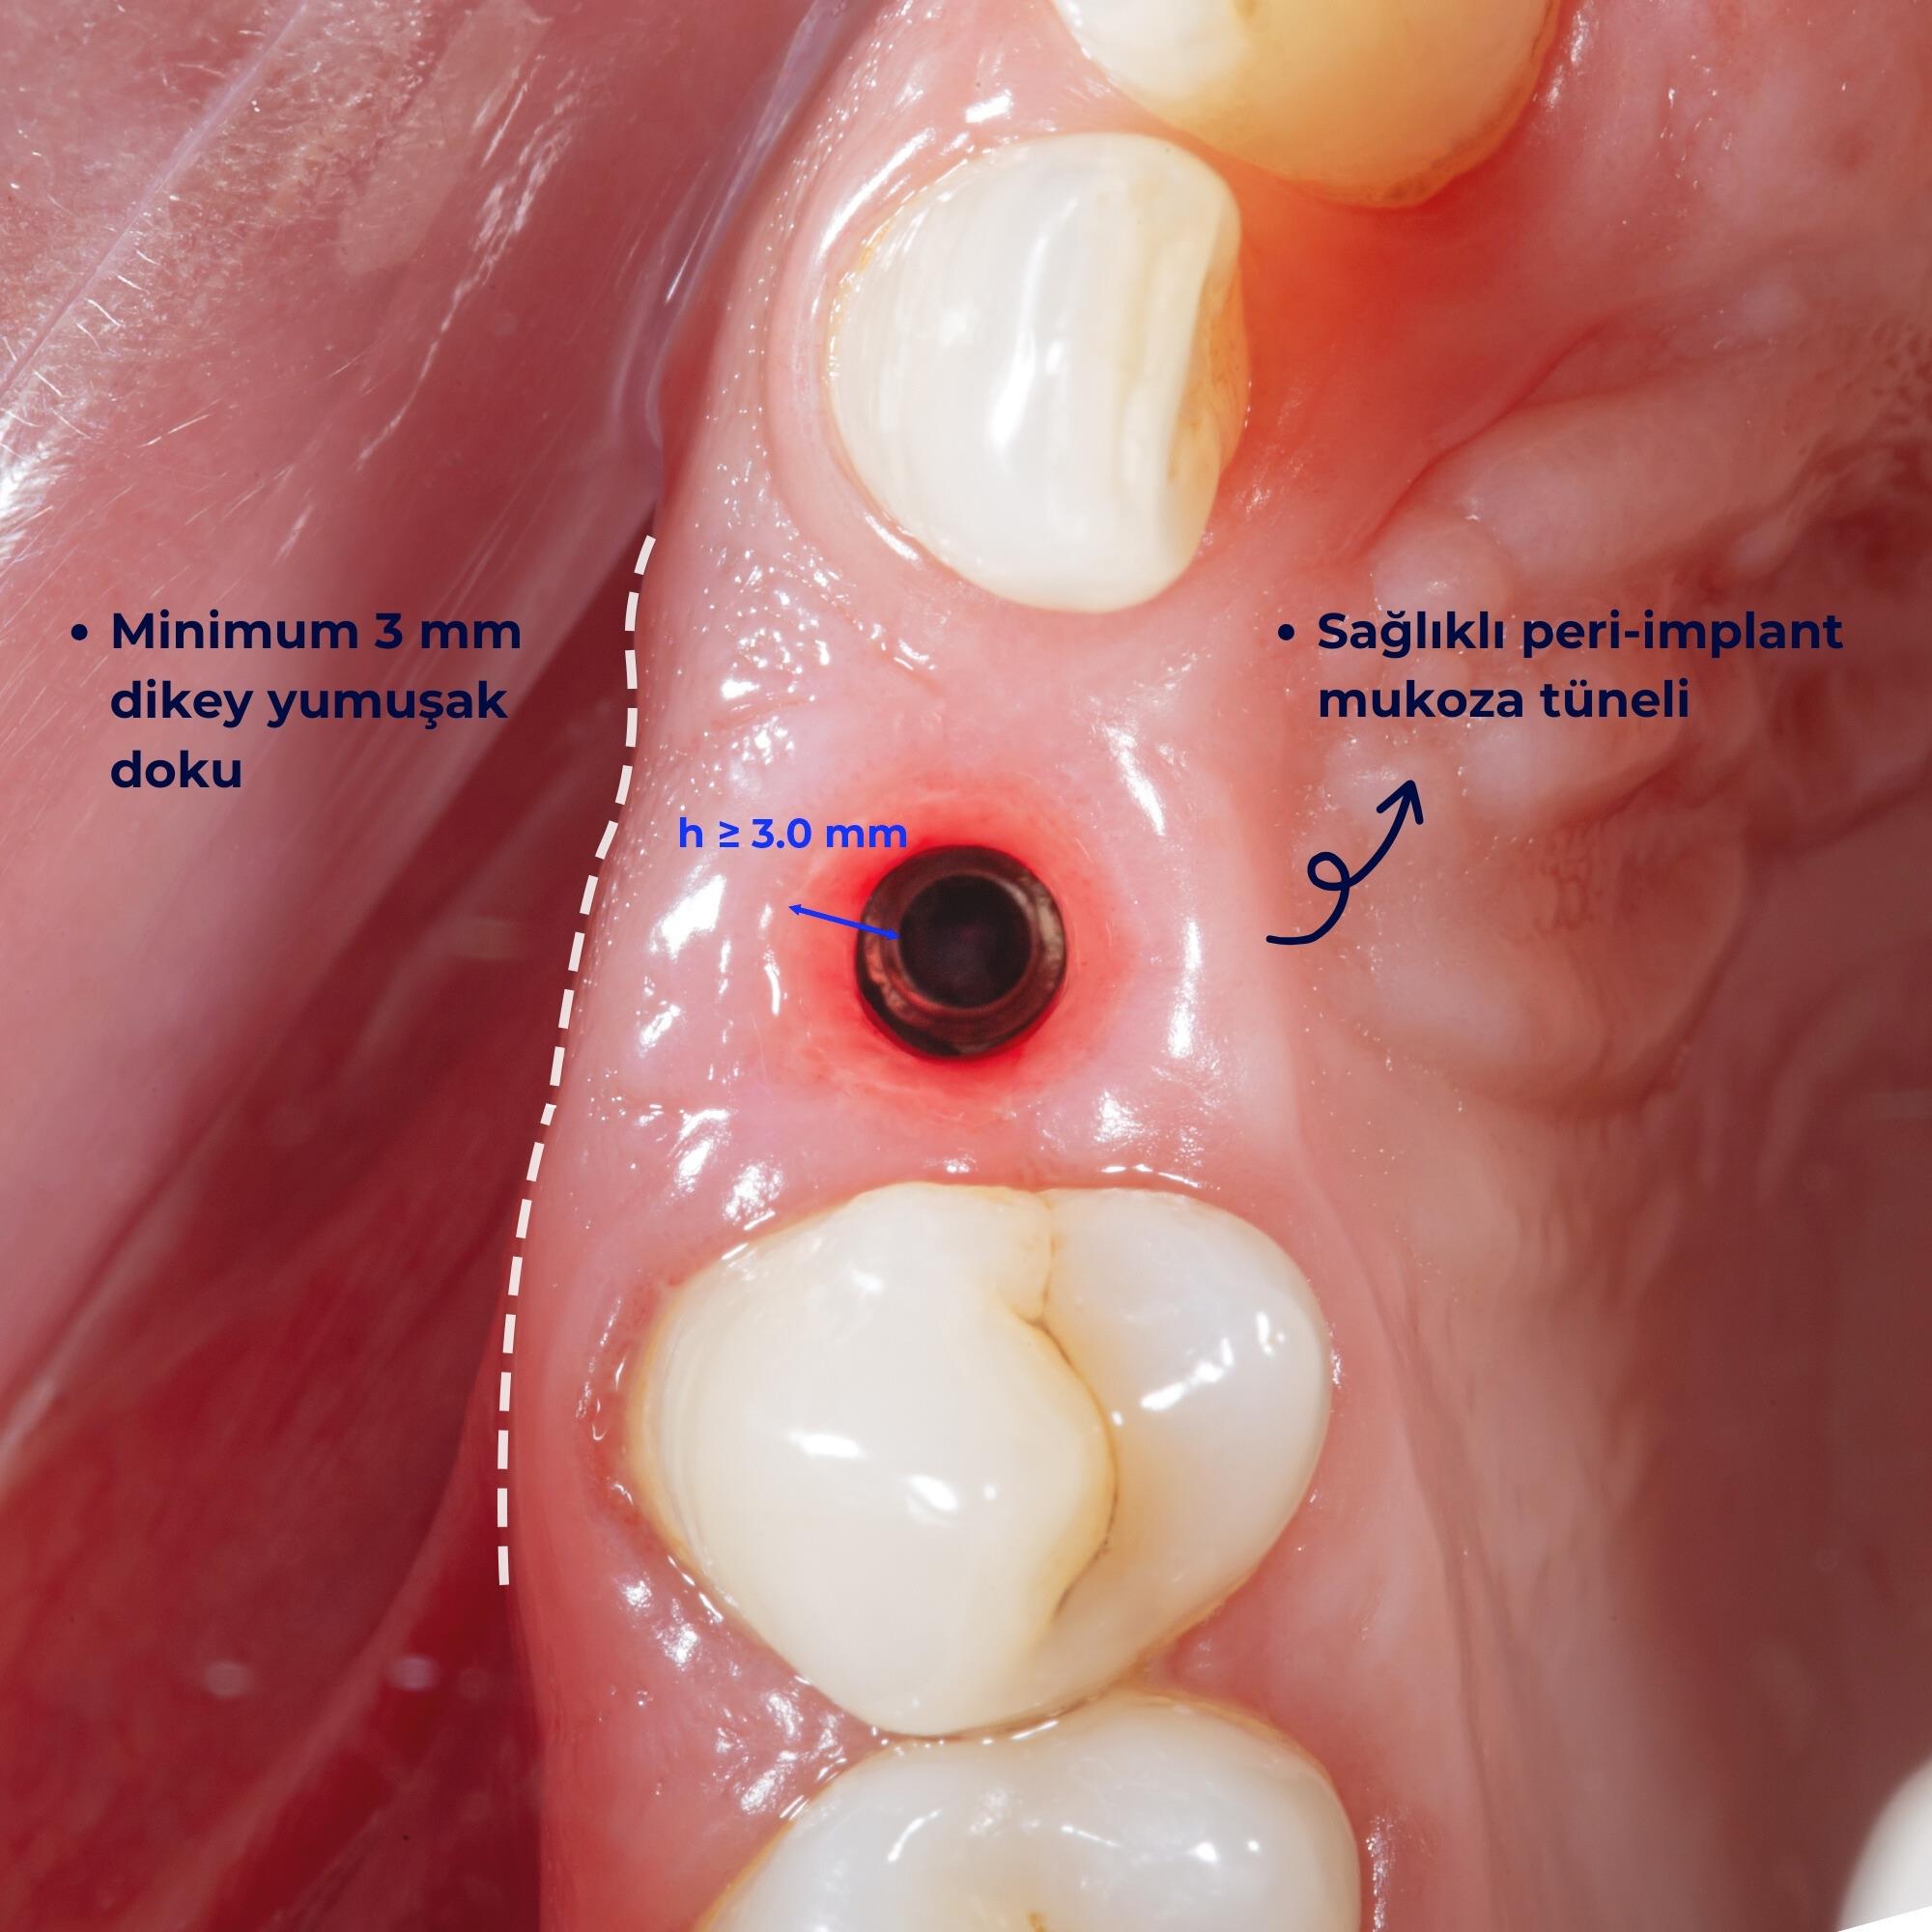

Başarılı bir implant tedavisi için kriterler nelerdir?